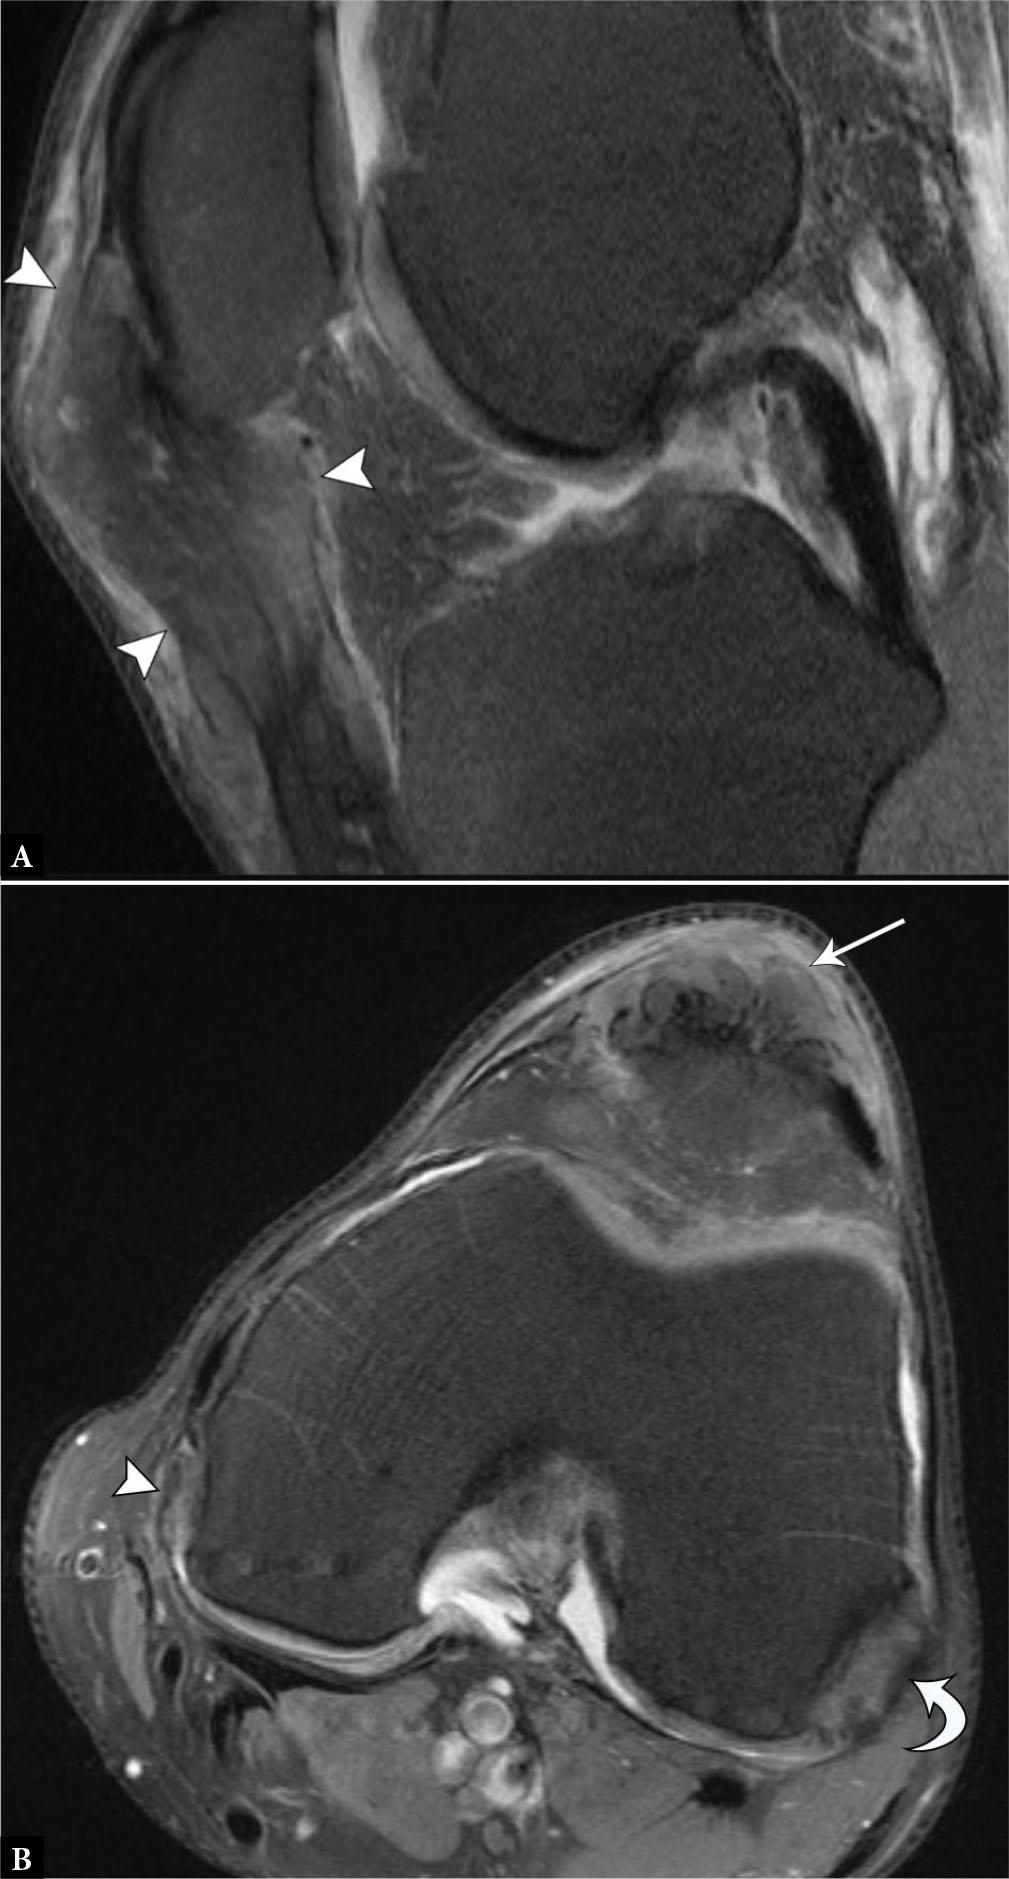

At US, collateral ligament injuries range from hypoechoic ligamentous thickening, partial fiber disruption, or a full-thickness tear with interposed fluid and heterogeneous debris (Fig. 10). In the setting of distal MCL tears, it is important to assess the relationship of the torn ligamentous fibers and the overlying pes anserinus to identify a Stener-like MCL tear. With this injury, the torn and displaced MCL fibers are superficial to the pes anserine tendons, preventing adequate healing and necessitating surgical repair to restore stability (Fig. 11)(31). For partial-thickness or non-displaced complete tears, shear wave elastography and power Doppler imaging may prove useful to assess collateral ligament healing, particularly in high-performance athletes(32,33). Laxity of an injured ligament is associated with decreasing shear wave velocities, or “softening” of the ligament, and may be associated with a functional decline(32). A biomechanical elastography study identified the greatest relative stiffness of the MCL during full knee extension and suggested that return to play could be determined by loading the injured collateral ligament at progressively lower flexion angles, while assessing for gradually improving ligament stiffness(34). Comparison to the stiffness of the uninjured contralateral side provides a valuable reference range. Ongoing studies continue to explore the clinical significance of elastography in monitoring recovery and risk of recurrent injury in athletes.

Fig. 11.

A. 19-year-old male with displaced MCL tear. Coronal proton-density-weighted fat-suppressed MR image shows completely torn and proximally displaced MCL stump (curved arrow) superficial to the pes anserinus, consistent with a Stener-like lesion. B. 16-year-old male with flipped and entrapped MCL tear. Coronal proton-density-weighted fat-suppressed MR image shows completely torn and proximally displaced MCL stump entrapped at the medial joint line inferior to the meniscus (arrow), which also requires surgical repair despite lying deep to the pes anserinus.

A recent systematic review identified MRI as the most common imaging method for evaluating collateral ligament injuries(35), and MRI is considered the imaging gold standard(28). According to this review, MRI fared well in grading injury severity, but detected the location of injury less reliably, particularly with obliquely oriented MCL ruptures(35). Another recent study noted only a “fair” agreement between MRI and the clinical grade, with MRI frequently overestimating the injury grade(36). Despite these shortcomings, there was a notable degree of consensus with respect to the diagnosis and localization of the surgically-significant Stener-like lesions(37).

On MRI, the ligaments are hypointense structures and pathology is visualized as intrasubstance hyperintense edema and fluid on fluidsensitive sequences. If concerned about isolated collateral ligament injuries, US functions well for focused examinations, with a diagnostic accuracy for MCL injuries of up to 94%(38).